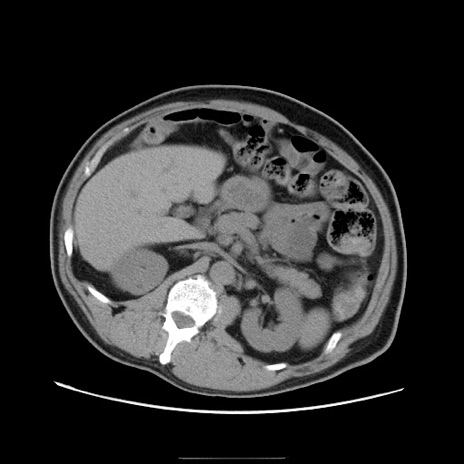

症例22(横断像)

【症例】50歳代男性

【主訴】腹痛

【現病歴】AVMからの被殻出血のため回復期リハ病棟入院中。 本日午後3時頃急に下腹部痛が出現した。

【既往歴】AVM、被殻出血、虫垂炎、高血圧

【身体所見】意識晴明、左半身不全麻痺、会話の理解は良好、36.5°C、腹部:膨隆、全体に板状硬、下腹部正中に圧痛点あり、反跳痛-、筋性防御不明、右下腹部にope scar

【データ】WBC 9400、CRP 0.06